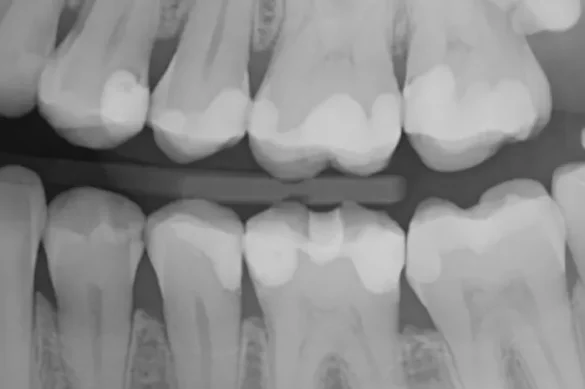

Bitewing X-rays are a kind of dental radiograph normally used for the duration of ordinary dental appointments. The manner entails the affected person biting on a wing-formed holder that positions a sensor or film, permitting the X-ray device to seize specified photos of each the top and decrease enamel at once. These photos spotlight the crowns of the enamel and the bone degree among them, presenting important data unseen for the duration of everyday visible exams.

When the X-ray photograph is produced, wholesome enamel fabric absorbs greater radiation and indicates up as lighter regions, at the same time as cavities—due to the breakdown of enamel—take in much less and seem darker. This assessment permits dentists to pinpoint spots of decay, inclusive of the ones hidden below restorations or on the touch factors among enamel.